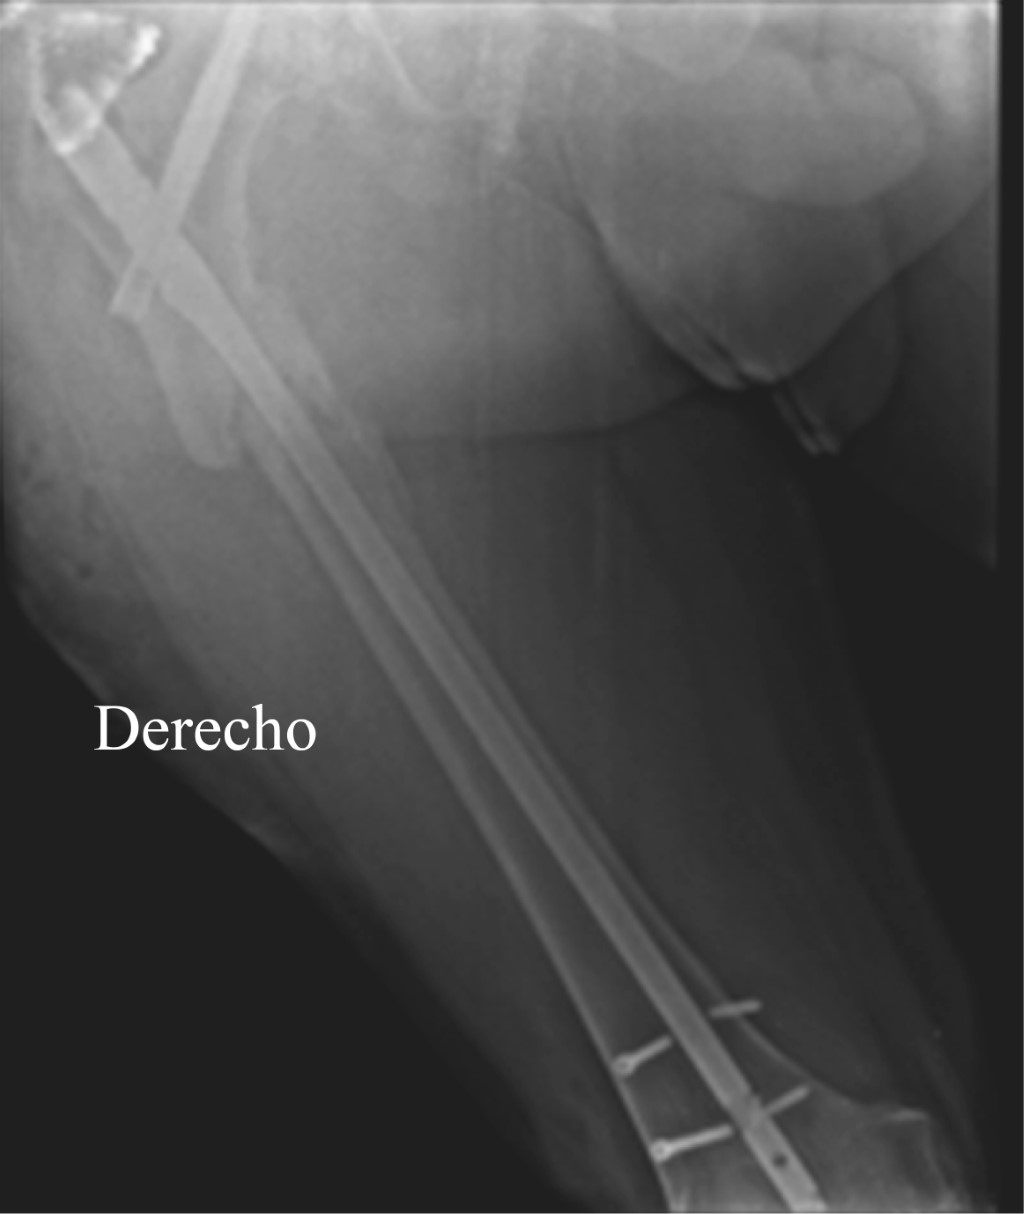

En Mayo de 2020 por persistencia de la infección se retira el material de osteosíntesis, se deja un clavo TENS endomedular recubierto de cemento con antibióticos (gentamicina) (Figura 5). A finales de Mayo después de dos lavados quirúrgicos se retiró el clavo TENS, resección de bordes de fractura (hasta hueso sano) injerto óseo endomedular con un segmento de 10 cm de peroné no vascularizado (autólogo) y fijación de la fractura con una placa de soporte condíleo de fémur distal (Figura 6); colocación de sistema VAC y cierre definitivo de la herida en un segundo tiempo el 28 de Mayo de 2020.

Figura 6